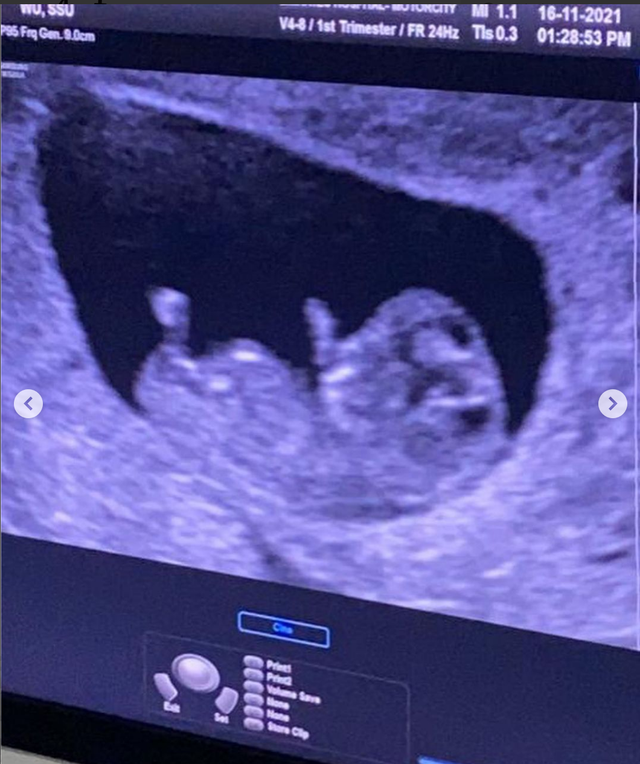

吴思颜同时分享了自己的B超照 , 小宝宝在她的肚中已经成形 。 她透露自己的第二胎肚子大得有些快 , 而且已经知道了宝宝的性别 , 但她还未打开信封 , 所以结果尚未揭晓 。